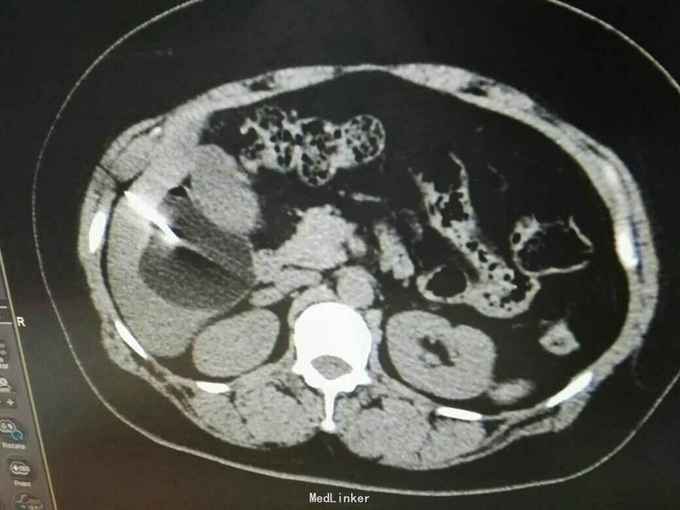

巨大肝囊肿

发现肝脏占位10年

肋弓下可触及囊性占位

肝囊肿

今日在局麻下行囊肿穿刺抽吸+无水酒精注射术 术中共抽取淡黄色液250ml